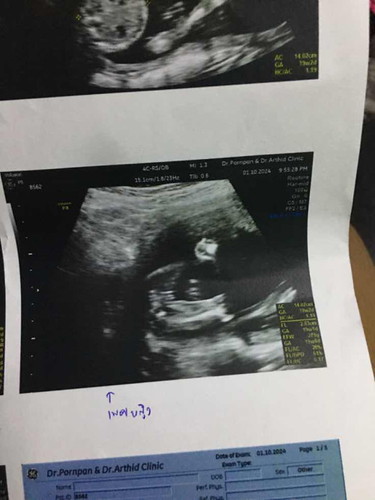

อัลตราซาวด์เพศลูก

รบกวนแม่ๆช่วยดูหน่อยค่ะ คุณหมอบอกว่าเป็นผู้หญิง บางทีแม่คิดว่า แอบเหมือนผู้ชายค่ะ ขอบคุณล่วงหน้านะคะ